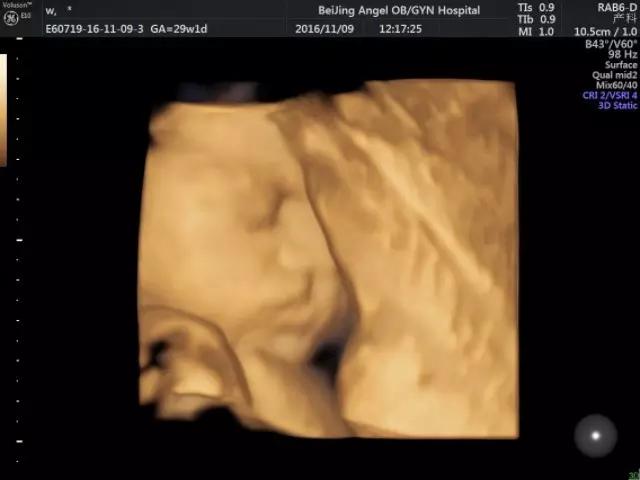

安琪E10四维彩超下宝宝萌态

四维彩超是目前世界上先进的彩色超声设备。四维彩超能够表面成像,可以更佳清晰的查出来胎儿的四肢发育是否畸形,脑膜膨出,是否唇腭裂、脊柱裂等先天畸形,及早发现及早的做出解决方案。

四维彩超可自动为胎儿进行“深宫”照相及生成动态图像,让准爸妈能清新一睹宝宝“宫”内举动和乖巧秀容,安琪超声科还可让家属陪同观看,尽享温情的亲子时光。